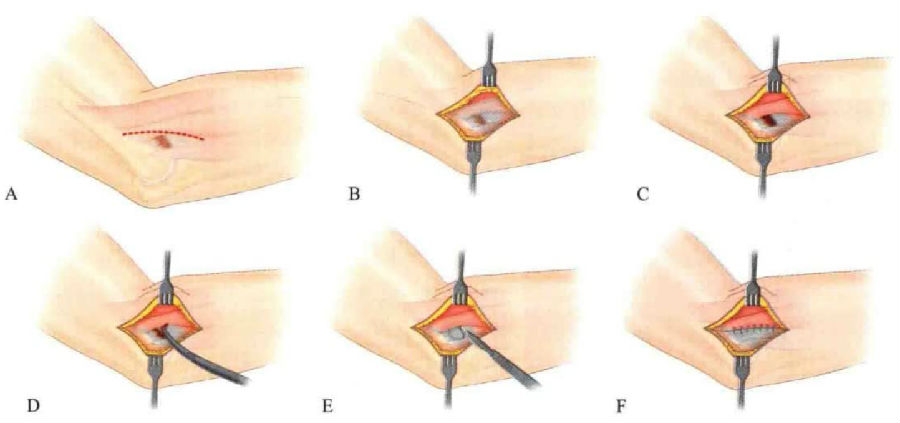

既往的切开手术有多种方式,应将所有病变组织一并去除。手术采用外侧切口,切开皮肤及皮下组织后,寻找桡侧腕长伸肌与指总伸肌,在两者之间进入并显露桡侧腕短伸肌,将其自肱骨外上髁起点处以锐刀剥离并翻转,判断病变组织范围后彻底切除。有人提出在外上髁骨皮质上钻2~3个深达松质骨的孔,目的是使局部形成血肿,促进血管及健康的肌腱纤维长入,但目前尚无定论该操作确实有效。将不同伸肌之间的筋膜组织缝合,逐层关闭伤口(图7)。

图7 切开手术过程灶

A、肘关节外侧切口;B、切开皮肤及皮下组织后,可见损伤位于桡侧腕长伸肌深方;C、在其深方显露桡侧腕短伸肌,显露病灶

D、对病灶进行清理;E、完整切除病变组织 ;F、缝合正常肌肉及筋膜